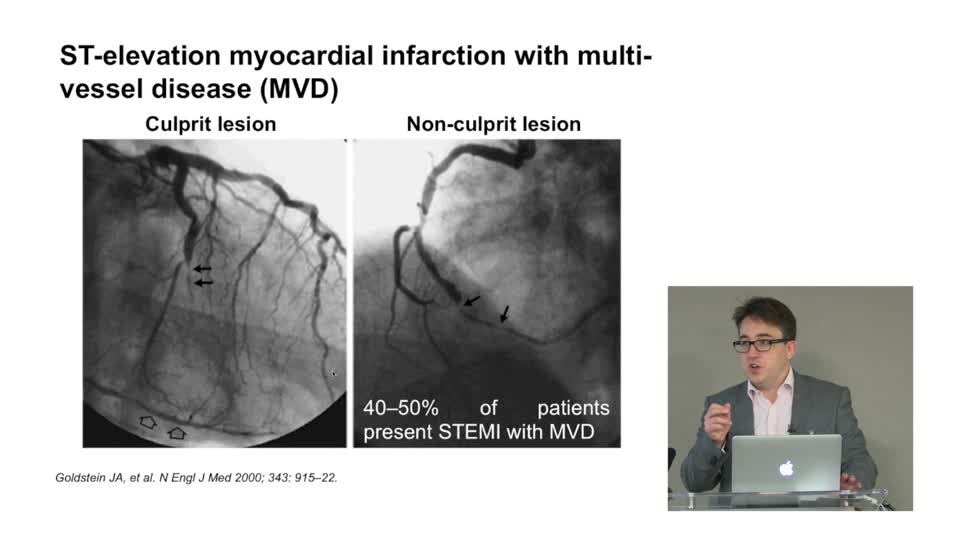

Spotlight Discussion: Management of multivessel disease in patients with acute coronary syndromes